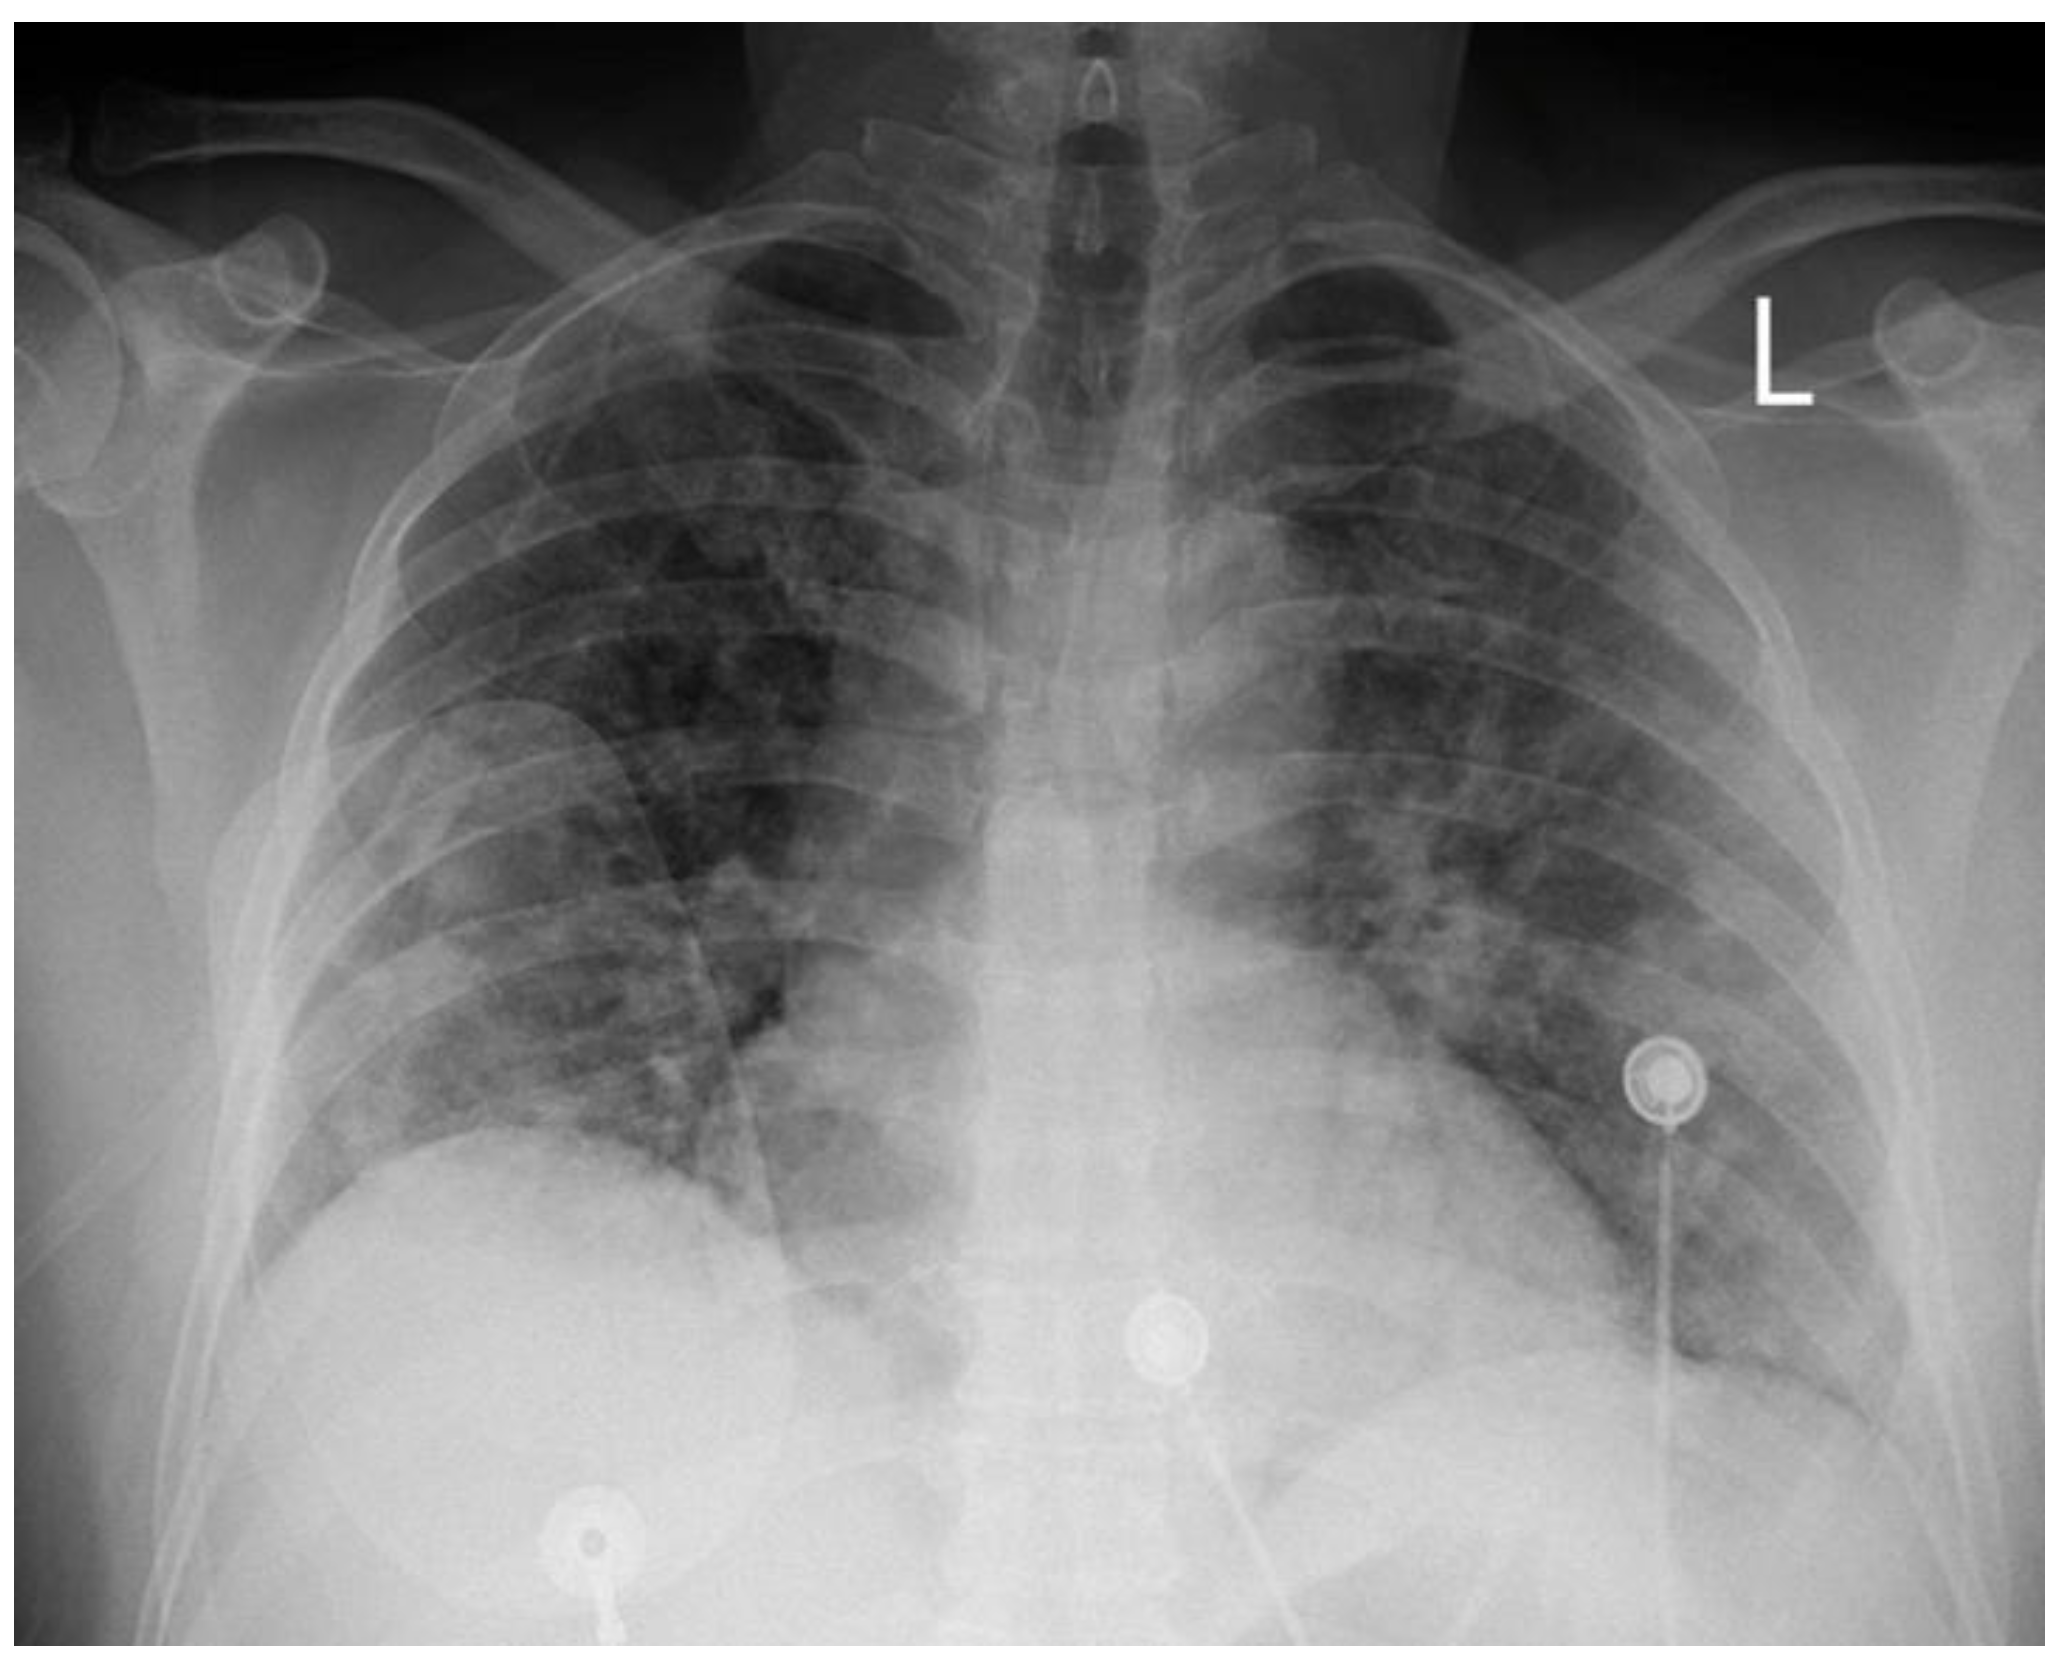

At the one-month follow-up, the patient remained uncomplicated. The echocardiographic study demonstrated full recovery of systolic function with no hypokinesia present. The repeat angiographic image was also significantly improved (Figure 4). Rivaroxaban was discontinued and the patient was advised to continue ASA for at least a year. He was also subjected to computed tomography angiography from the brain to pelvis, as part of the screening for extracoronary arteriopathies (especially fibromuscular dysplasia), which did not reveal abnormal findings. Laboratory analyses after one month from the acute infection, including antinuclear antibodies, antibodies to β2-macroglobulin, and rheumatoid factor, were also negative, excluding the presence of chronic systemic inflammatory disease.

Figure 4. Repeat coronary angiography of the LCX, revealing angiographic healing. The red arrows show the improvement of the previously affected vessel sections. (a) RAO cranial angiographic view; (b) RAO caudal angiographic view.